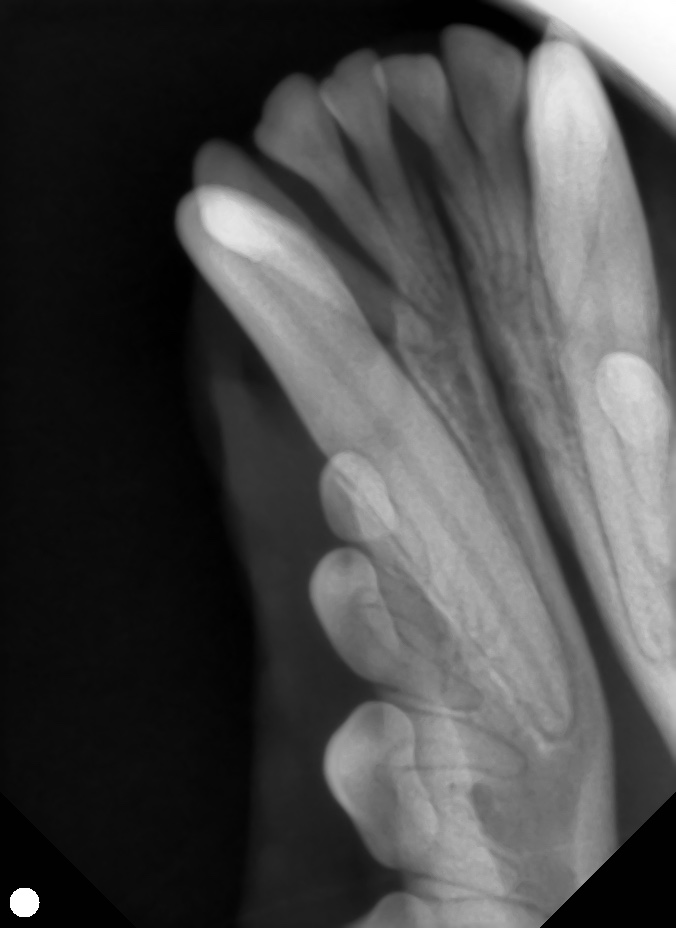

- 歯科レントゲン検査で、右下顎第三切歯に骨融解を確認

また、下顎犬歯と上顎切歯の不整咬合も認めました。